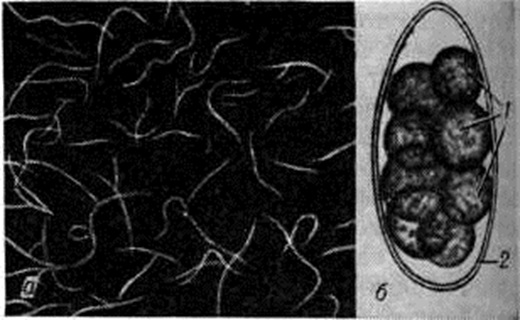

Возбудителем Трихостронгилоидоз являются мелкие нематоды из семейство трихостронгилид (Trichostrongylidae Leiper, 1912), среди которых выделяют 12 видов. У человека Трихостронгилоидоз в большинстве случаев обусловлен инвазией двух видов — Трихостронгилоидоз orientalis и Трихостронгилоидоз colubriformis. Все остальные виды трихостронгилид обычно инвазируют жвачных животных и у человека паразитируют редко. Трихостронгилиды — нитевидные нематоды длиной около 5 миллиметров(рисунок, а). Виды трихостронгилид различаются по особенностям строения тела самцов.

Трихостронгилиды — геогельминты (смотри полный свод знаний). Их облигатными хозяевами являются многие травоядные животные, главным образом крупный и мелкий рогатый скот, в пищеварительном тракте которых они паразитируют. У человека (факультативного хозяина) трихостронгилиды паразитируют в тонкой кишке, чаще в двенадцатиперстной кишке, проникая своим передним концом в слизистую оболочку. Самки трихостронгилид откладывают сегментированные яйца длиной 0,075—0,118 миллиметров, содержащие 8—24 бластомера (рисунок, б); яйца попадают в окружающую среду с фекалиями. При благоприятных условиях в яйцах в течение нескольких суток развиваются рабдитовидные личинки. В дальнейшем личинка дважды линяет и превращается в инвазионную филяриевидную личинку с чехликом. Проглоченная животным или человеком инвазионная личинка в кишечнике претерпевает ещё две линьки и, не совершая миграции, развивается в зрелого паразита приблизительно через 3 недель после заражения. Указывают на возможность длительного, до 8 лет и более, течения этой инвазии. Интенсивность инвазии может быть высокой — до 4 тысяч трихостронгилид.

Рис

Взрослые особи (а) и яйцо (б) Trichoslrongylus colubriformis: 1 — бластомеры, 2 — оболочка.